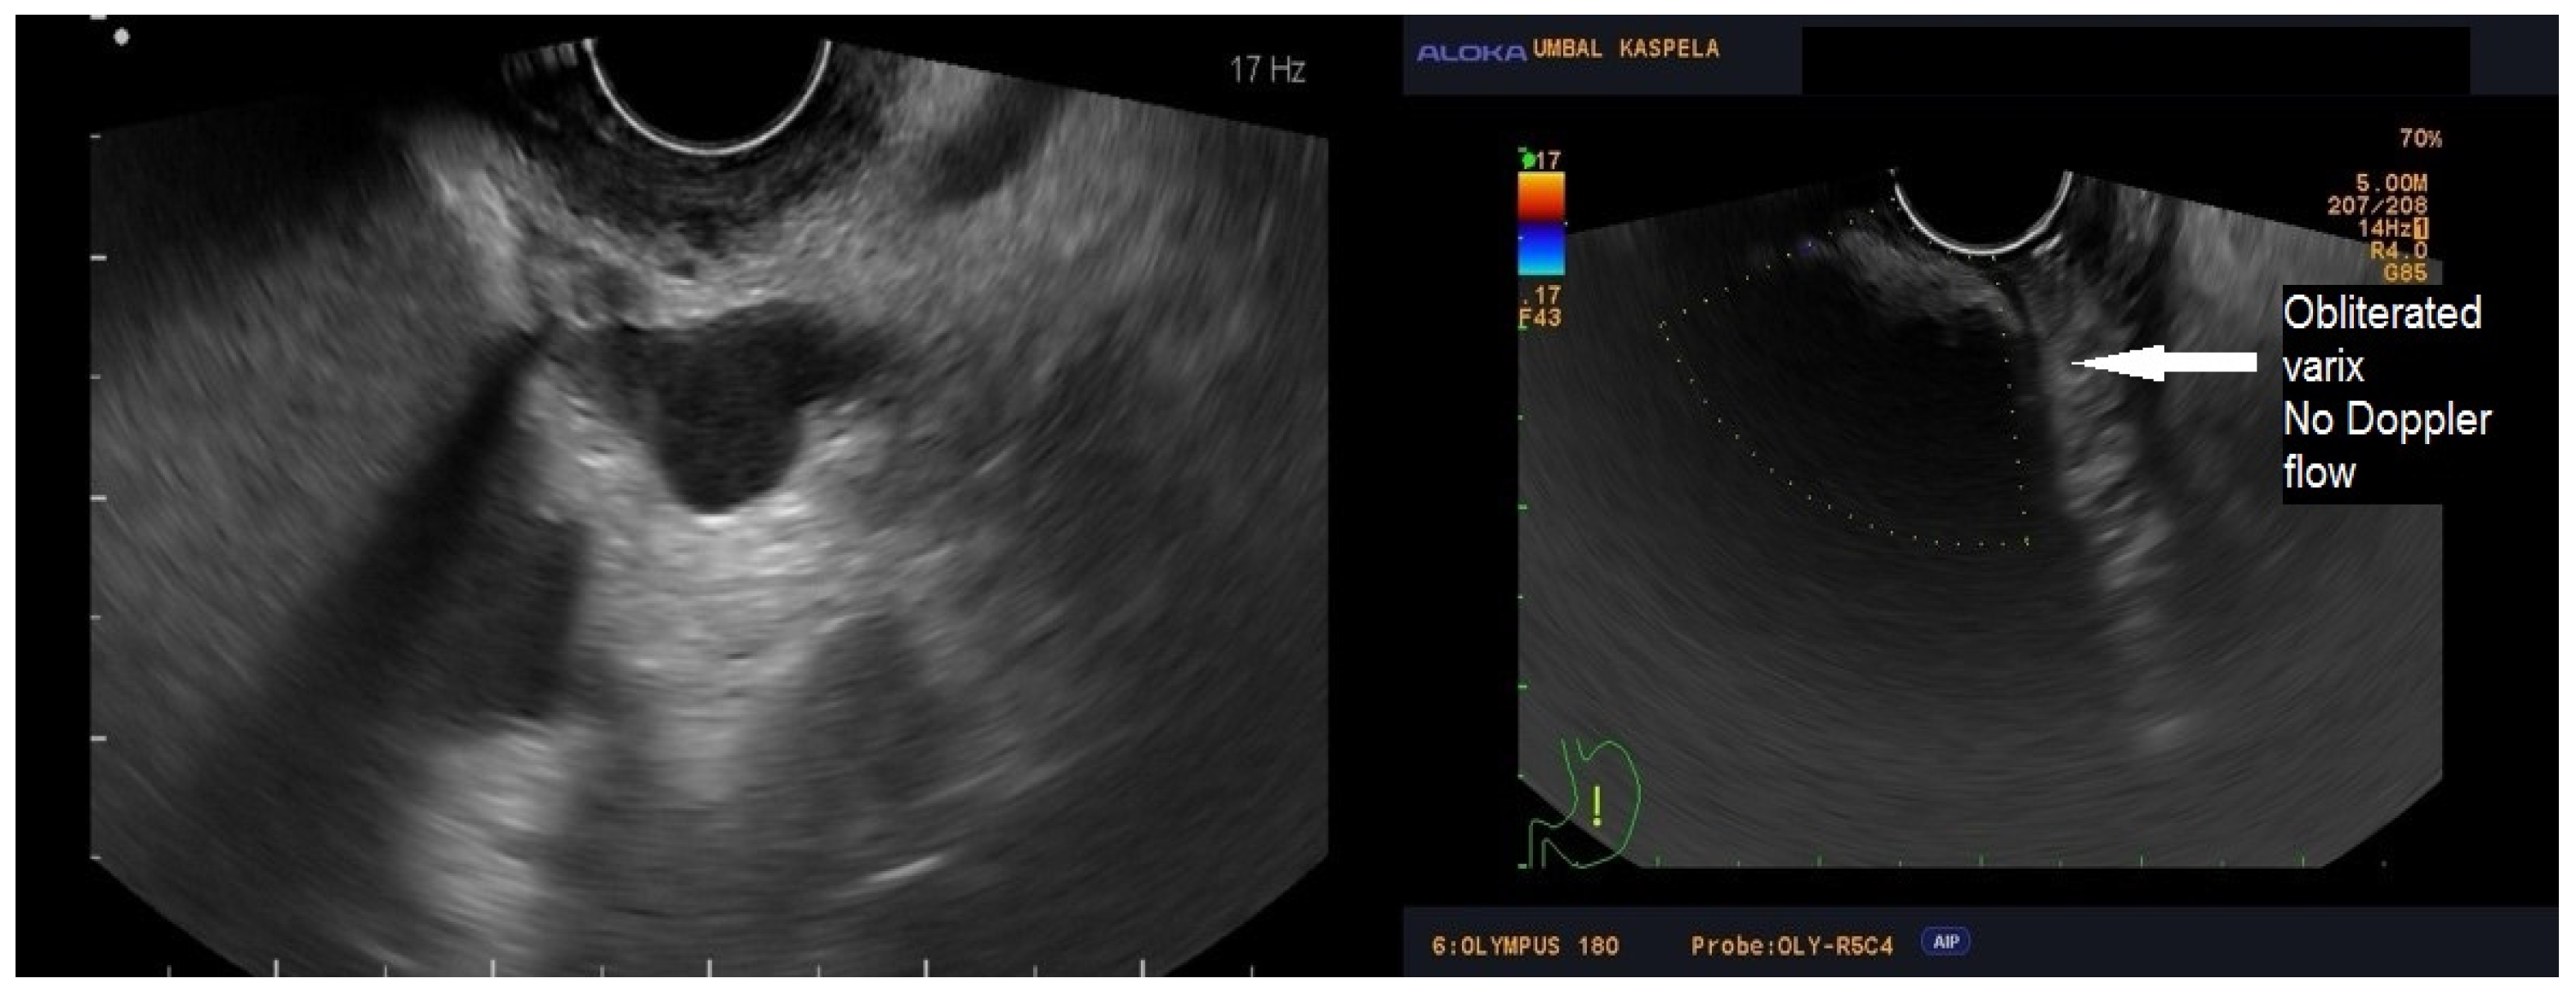

Figure 1, Figure 2 and Figure 3 present post-procedural endoscopic, endosonographic, and fluoroscopic findings.

Figure 2.

Ultrasonography showing absent Doppler flow in the treated vessel.

A follow-up endoscopy was performed 30 days after the intervention. The Doppler EUS showed no blood flow in the gastric varices. According to the existing guidelines, EBL (Super7; Boston Scientific, Marlborough, MA, USA) of EVs was electively performed to achieve eradication. Upper endoscopies were performed at 3 and 6 months without progression signs of GOV.